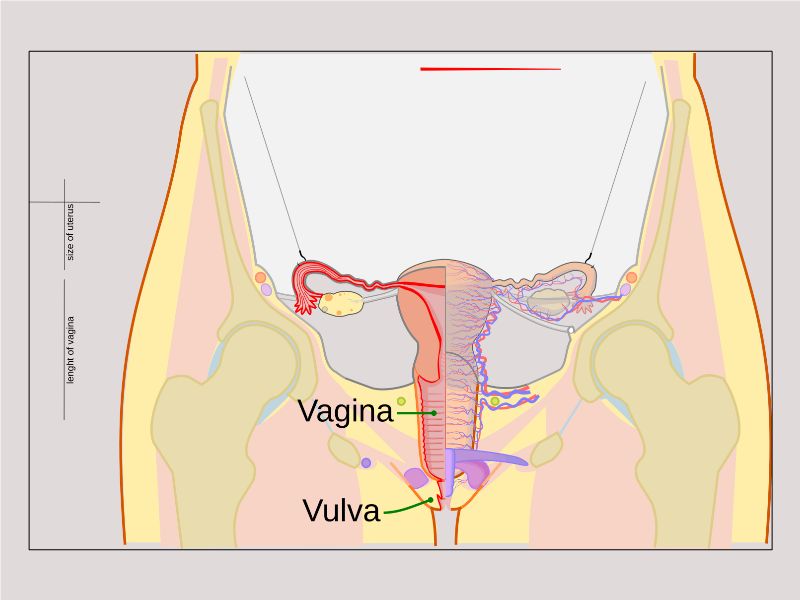

Vagina

Slide 90

Vagina

- Fibromuscular tube with 3 layers

- Inner mucosa

- Middle muscle layer

- External adventitia